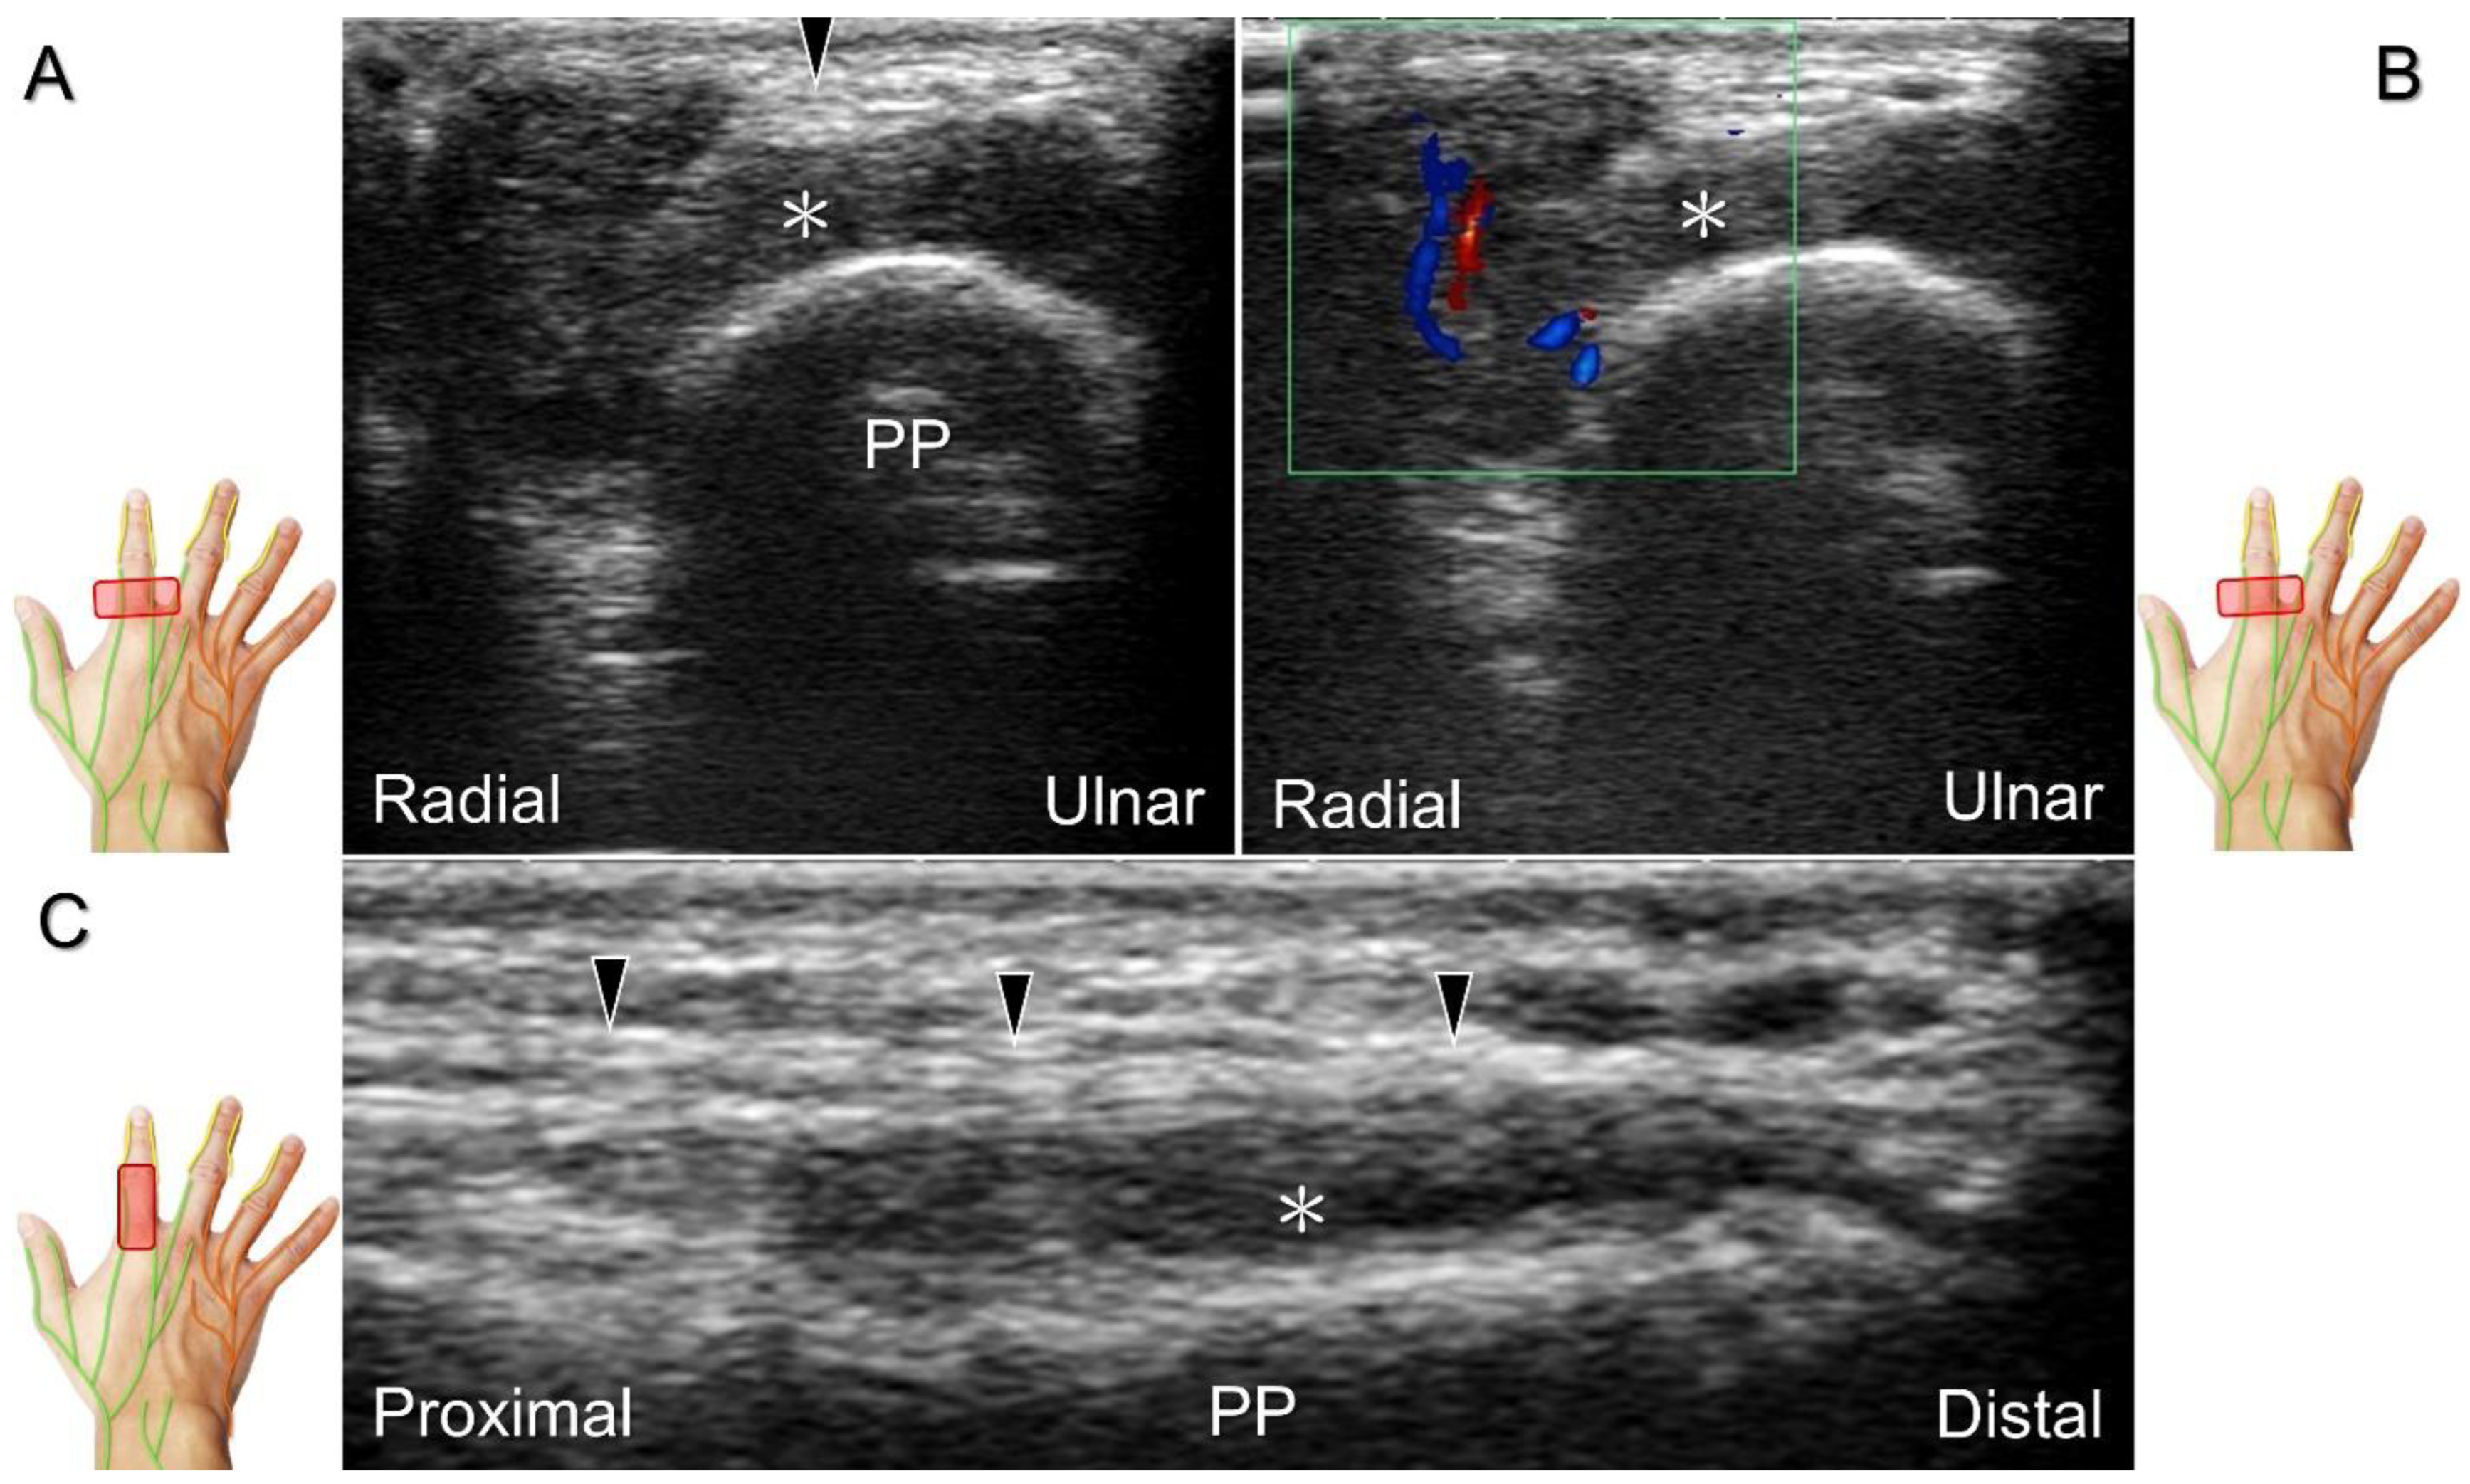

Figure 30. In comparison to the healthy side (A), short-axis imaging (B) shows irritation of both the palmar and dorsal proper digital nerves due to a fibroma (asterisk). Short-axis (C) and long-axis (D) imaging demonstrates irritation of the palmar proper digital nerve due to a hemangioma. Spectral Doppler mode (E) confirms the hemangioma. White arrowhead: palmar proper digital nerve; black arrowhead: dorsal proper digital nerve; double asterisk: hemangioma; PP: proximal phalanx.

Clinical Implication

Direct injury of the palmar common digital nerve can occur due to various reasons such as trauma, contusion, or iatrogenically during tendon injection. Nerve entrapment caused by space-occupying lesions such as fractures, ganglia (Figure 29A–C), annular ligament tears (Figure 29D), tenosynovitis, foreign bodies, fibroma (Figure 30A,B), or hemangioma (Figure 30C–E) is also likely.